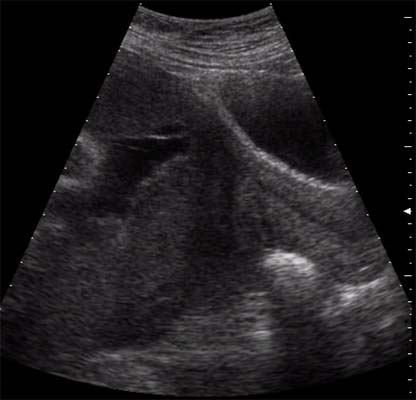

Hématome rétro-placentaire :

Clivage par un hématome de l’espace virtuelle entre la plaque basale et la paroi utérine.

Massif, il décolle presque totalement le placenta et entraîne une symptomatologie maternelle bruyante et la mort fœtale. L’échographie montre alors un placenta flottant sur un caillot ou une vaste lacune anéchogène.

De volume plus réduit (n’excédant pas plus du quart de la surface placentaire), il évolue sous forme d’une MAP hémorragique ou sous forme d’une souffrance fœtale.

Hématome organisé :

- Echogénicité voisine de celle du placenta mais souvent moins homogène

- Siège au niveau basal

- Le soulèvement de la plaque basale est évident lorsqu’elle est calcifiée

- Parfois se réduit à un simple épaississement localisé du placenta ?

Hématome marginal :

L’hématome se forme sous le bord du placenta et diffuse sous les membranes adjacentes. Plus fréquent en cas de placenta inséré sur le segment inférieur (rupture d’une veine utéro-placentaire).

Cliniquement, possibilité de métrorragie ou de contractions utérines. Le pronostic fœtal n’est pas engagé. L’évolution ne se fait que très rarement sous le placenta pour constituer un HRP.

Echographiquement : Volumineux caillot échogène soulevant les membranes en bordure du placenta. Il finit par se lyser pour ne laisser qu’un soulèvement anéchogène des membranes qui régresse en quelques semaines.